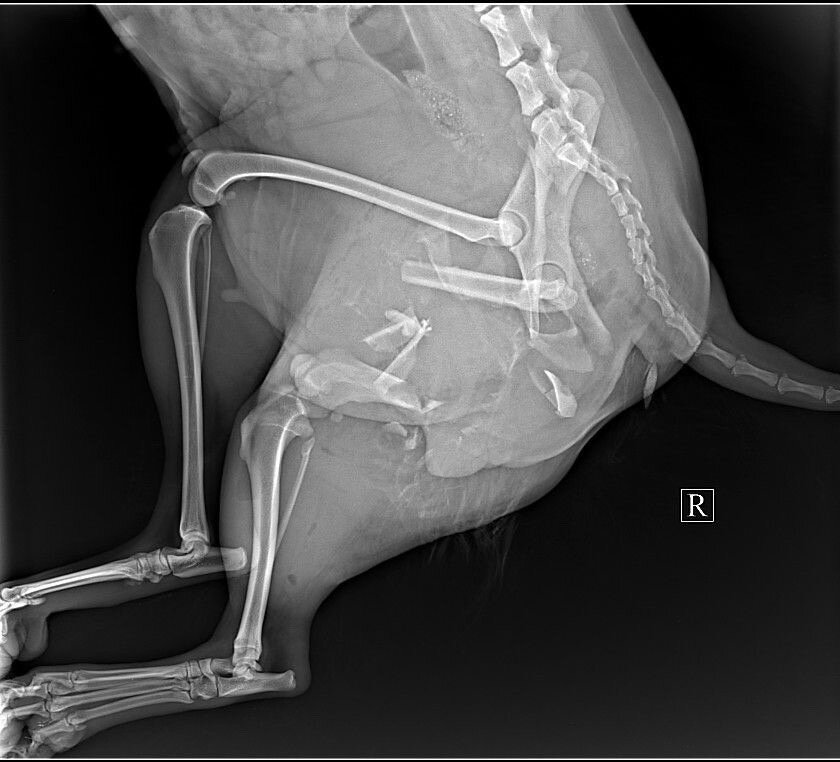

Очень ВАЖНЫЙ СБОР, для сбитой собачки! Диагноз у Дафни: оскольчатый перелом подвздошной кости (с права) и ПЕРЕЛОМ ТАЗА. За такую сложную операцию никто особо из тех докторов, кто вызывает у нас доверие-не брался. А Спартак Анатольевич (Биота) был не в городе, пришлось ждать. В итоге срочно прооперировали собачку, помните, собирали с вами денежки на оплату операции, когда Дафни была уже на операционном столе. Божечки, вы нам так помогли! Мы оплатили ПЕРВУЮ операцию в клинике!

Но, борьба за НОРМАЛЬНУЮ жизнь на четырех лапках ПРОДОЛЖАЕТСЯ! Теперь нужно собрать такую же сумму 44 000 рублей на вторую операцию. Дафни будут делать остеосинтез, чтобы она смогла ходить! Если не собрать поломанный таз, собачка останется ИНВАЛИДОМ, и ходить уже не сможет никогда... И зачастую, у таких животных, НЕТ шанса найти ДОМ. А приют-это единственное спасение!